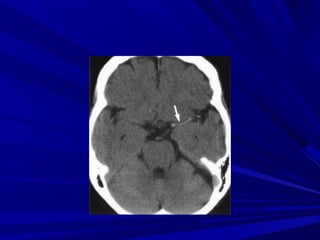

Leâ Vaên H., Nam, 44 tuoåi, Xuaát huyeát

thaân naõo

Traàn thò S., Nöõ, 73 tuoåi, Xuaát

XUAÁT HUYEÁT THAÂN NAÕOXUAÁT HUYEÁT THAÂN NAÕO